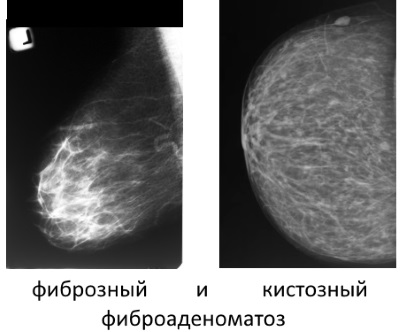

- Vatra. Acest subtip benigne a bolii este caracterizată prin faptul că țesutul glandular este treptat înlocuit fibros. Cea mai mare parte palpat sigiliu, dar acestea nu sunt întotdeauna dureroase, uneori, ele nu provoacă nici cea mai mică disconfort.

- Chistică. Cu varietate de boli apar multicompartimentală sigiliu de tip asemănător cu chisturi si avand contururi destul de buna.

- fibroadenomatosis fibrotice. În ciuda tautologia în titlu, acesta este, de asemenea, tipul de boală, care se caracterizează printr-o predominanță a creșterii țesutului fibros în timpul formării focilor în glandele.